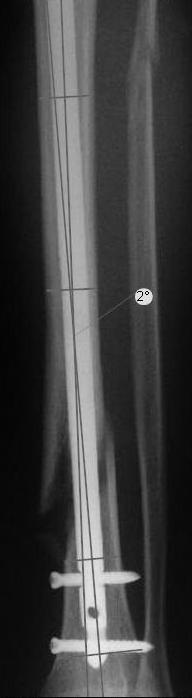

Вы бы стали оперировать или рекомендовали бы своему родственнику оперироваться из-за 2 градусов?

чтобы понять сколько там градусов, необходимо, как минимум, сделать осевые снимки. Я рассуждал по аналогии с протезами коленного сустава, вальгусное или варусное смещение более 3 градусов чревато ранней нестабильности. Почему же для нормального коленного сустава это должно быть хорошо?